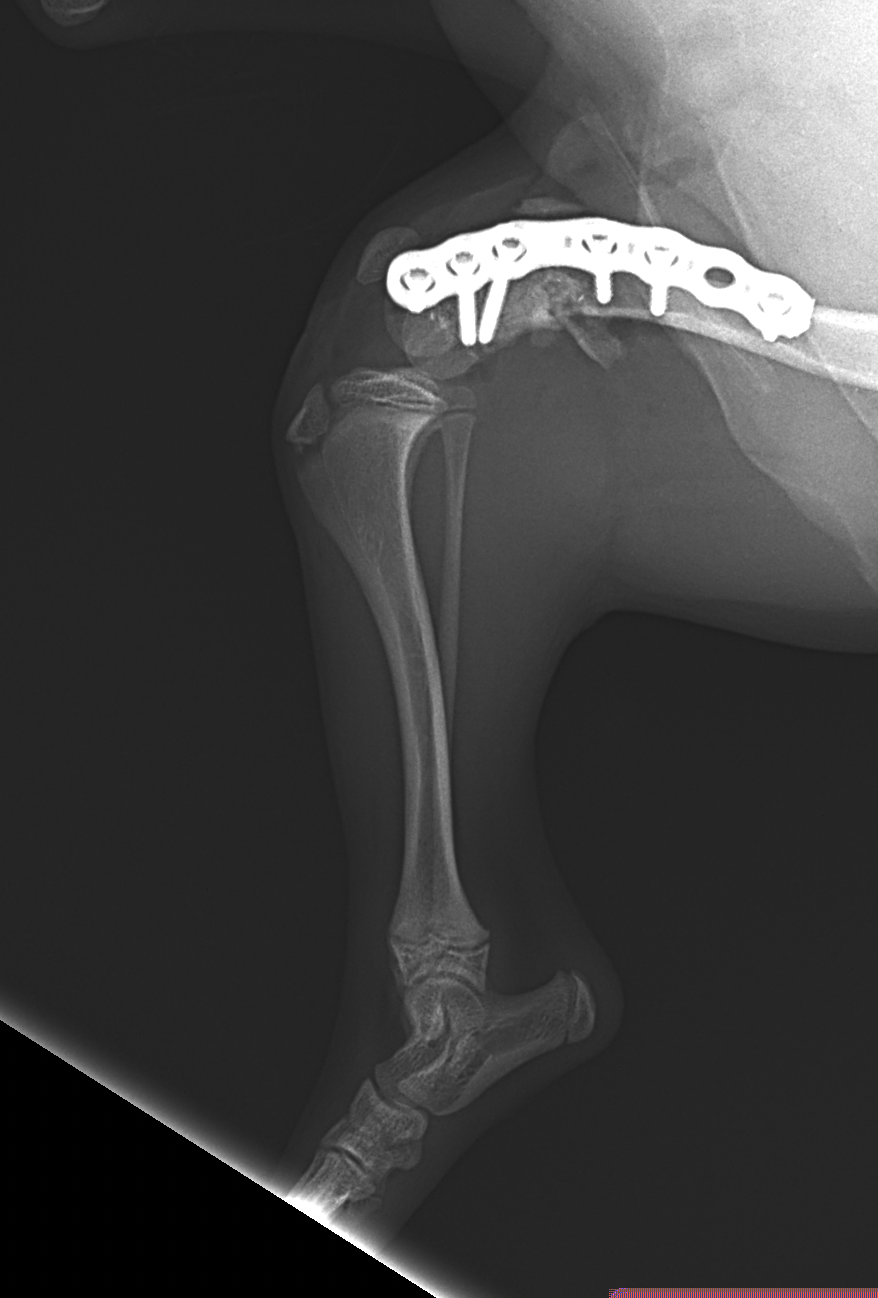

幼犬の大腿骨遠位の骨折です。幼犬は治癒能力が高く、仮骨の形成が早期に起こります。しかしながらこの時期は骨質が大変柔らかく固定には注意が必要です。本来であれば成長板をまたぐ固定は避けたいところですが、やむを得ず軽量のTitanium Locking Plateを用いて固定術を行いました。早期に抜釘することになります。